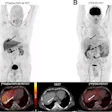

The system will also display the fused images as PET/CT over MR, PET over CT, CT over MR, and so on. The capabilities of the software can be viewed online at www.osirix-viewer.com.

The combination of PET and MR is particularly useful in radiotherapy planning, especially when treating tumors of the brain and prostate, and in some liver tumors that are treated with radiofrequency ablation. The software has also been tested to view bone metastases and in gated cardiac studies.

"PET shows the extent of metabolically active tissue in tumors, while MR shows the tissue alterations and the spatial distribution of surrounding organs. Unfortunately, very often MR does not show the exact extent of tumors due to surrounding inflammatory reactions and edema. Therefore, image fusion of PET and MR is expected to provide significant information that is not obvious from the two modalities presented separately; this can increase the accuracy and therefore confidence in diagnosis," Ratib added.